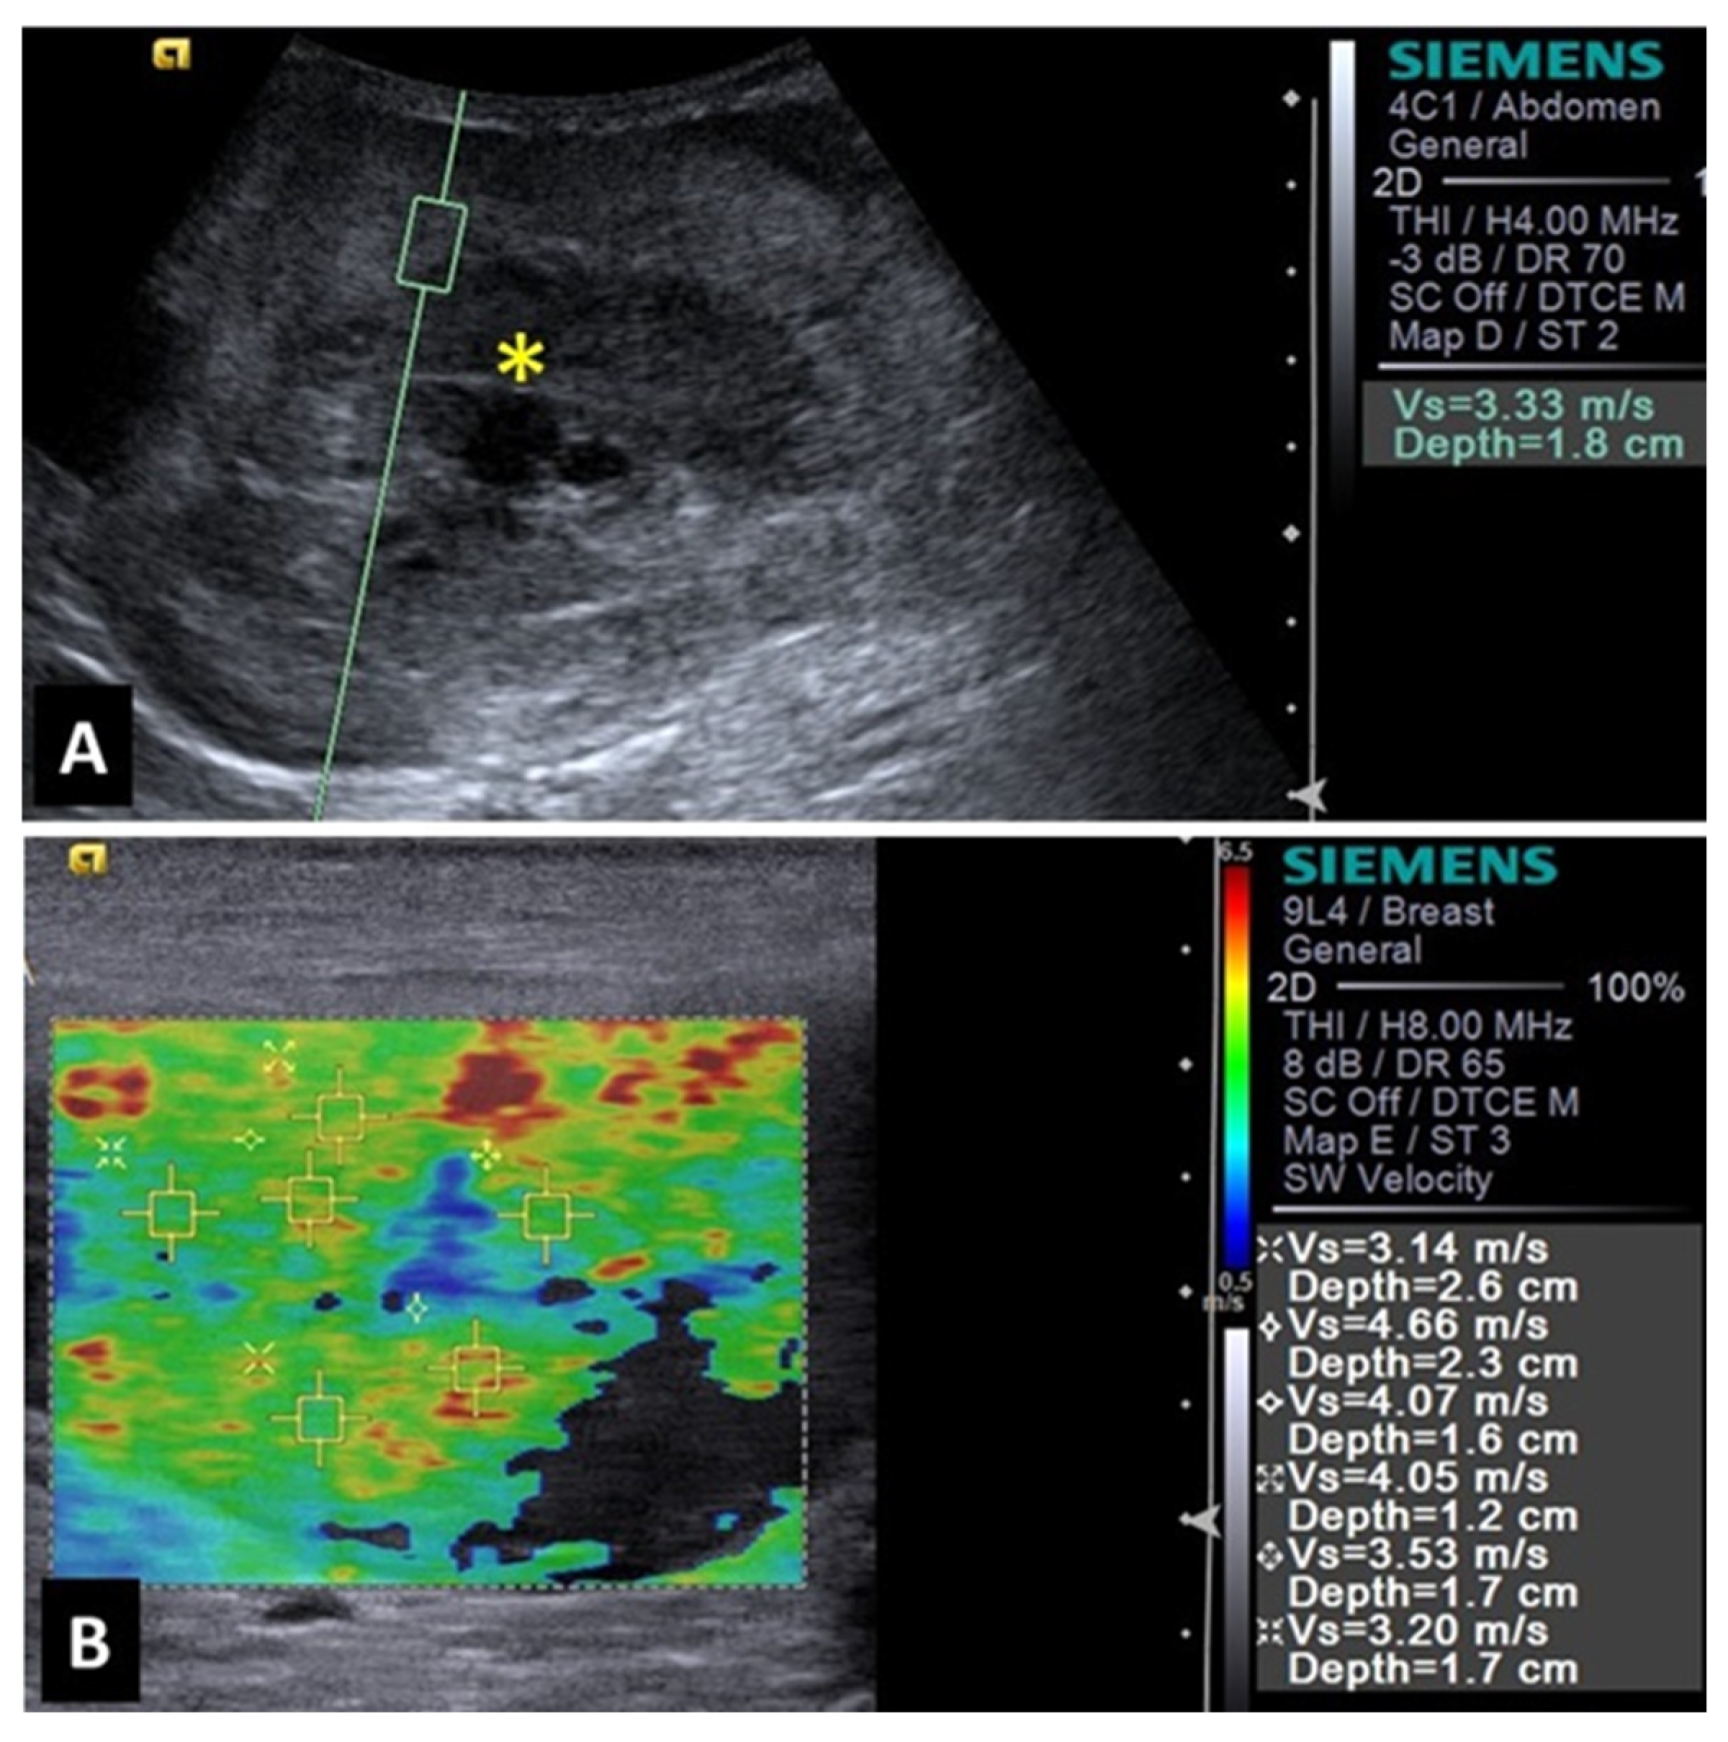

A study with elastography of canine mammary tumors was able to differentiate benign nodules (such as mammary hyperplasia, adenoma, fibroadenoma and mixed benign tumors) and malignant tumors (such as tubular carcinoma, complex tubular papilliferous carcinoma, mixed carcinoma, simple solid carcinoma, and complex carcinoma) [1]. This study reported that malignant mammary nodules were more rigid and, therefore, presented higher mean shear wave velocity (3,33 m/s), when compared to benign nodules (1,28 m/s).

ARFI elastography, as well as other imaging modalities, were used to investigate 300 mammary masses in dogs [22]. The authors described that shear wave velocity higher than 2,57m/s presented 94,7% sensitivity, 97,2% specificity and high accuracy for the detection of malignancy. Researchers clarified that the highest tissue stiffness and higher shear wave velocity of malignant mammary tumors can be explained by the stromal reaction induced by the carcinoma. They said that this event is associated with the increased amount of collagen fibers in the mammary tissue. Similarly, a study with Shear wave elastography reported lower shear wave velocity values for benign mammary nodules when compared to mammary tumors in dogs [23]. However, these authors highlighted that some benign and mixed malignant tumors can present ossified (more rigid) or cartilaginous tissues (less rigid), which could lead to a misdiagnosis.

Elastographic studies with domestic felines are scarce. Research with ARFI elastography of the mammary tissue of two female cats reported high shear wave velocity (cat 1 = 4,07m/s and cat 2 = 4,54m/s and 6,58m/s). The qualitative evaluation revealed rigid and non-deformable tissues. Those findings suggested the presence of malignant mammary tumors, confirmed by histopathological analysis as tubular carcinoma and cribriform mammary carcinoma [24].

Figure 1. Image of a benign splenic lesion (hematoma) in a dog: (A) B-mode of the splenic lesion with mixed and heterogeneous echogenicity; (B) ARFI elastography of the hematoma, demonstrating shades and shear velocity values indicative of decreased rigidity and benignity.